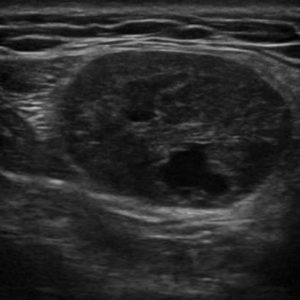

U tuyến nước bọt

Lượt xem: 153» 19-01-2021 -